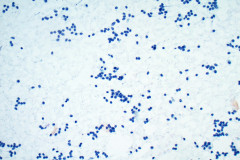

Cytology:

Aspirates of MTC are moderately cellular, showing a single cell pattern with occasional clustering and small aggregates. Cytologically, tumor cells can appear plasmacytoid, polygonal, or with spindle cells. Cells are uniform in size, but rare large pleomorphic cells may be present. The chromatin shows a coarse, granular, neuroendocrine pattern with inconspicuous nucleoli. Intranuclear inclusions may be seen, and nuclear grooves are rare. The cytoplasm is granular, and the amount is variable and rarely scant. Cytoplasmic dendritic processes may also be seen. Amyloid may be present in the background, although it can be identical to colloid in Papanicolaou-stained specimens. Variants of MTC include a follicular variant, papillary variant, small cell variant, giant cell variant, and a clear cell variant7. Cell blocks of MTC typically stain positive for calcitonin, CEA, TTF1, synaptophysin, and chromogranin, and are negative for thyroglobulin and PAX-88,9.

The tumor cells of this case presentation posed a diagnostic challenge due to their divergence from the typical cytological appearance of MTC. The majority of tumor cells had scant cytoplasm, including cells that resembled naked nuclei and cells with a plasmacytoid appearance. A diagnosis of MTC was rendered in conjunction with the patient’s elevated calcitonin level, history of MTC and MEN2, and comparison to the patient’s previous two MTC diagnoses.